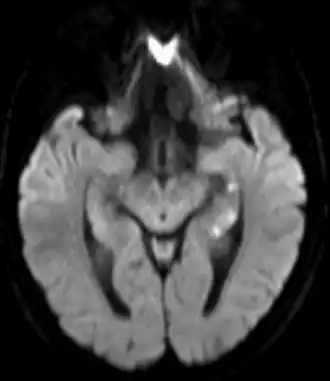

По данным МРТ может быть выявлена локальная ишемия в области гиппокампа и других структур головного мозга, отвечающих за память

Проведение МРТ помогает исключить острое нарушение мозгового кровообращения, наличие объемных образований и другую структурную патологию. При транзиторной глобальной амнезии могут быть выявлены очаги ишемии в гиппокампе.[12]

- Энцефалопатия Вернике и синдром Корсакова (на МРТ при Вернике: аномальный сигнал или изменения на DWI в медиальном таламусе, сосцевидных телах, околоводопроводной области и тектальной пластинке, реже в полушариях мозжечка)